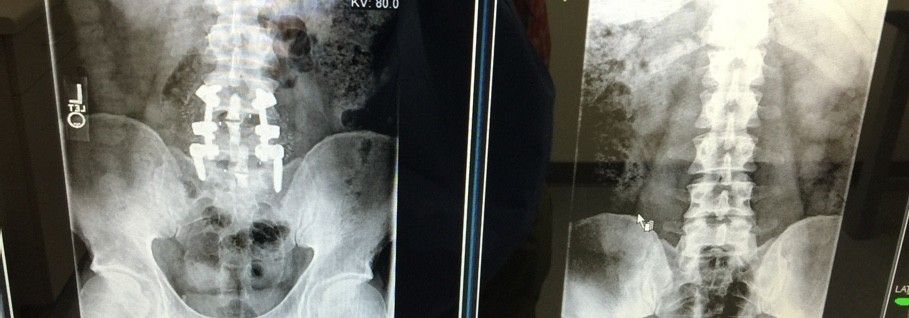

HOLY CRAP DUDE.......YOU GOT SCREWED!Here's my new titanium hardware. Should I compare it to the material that it replaced?

View attachment 135538View attachment 135539View attachment 135540